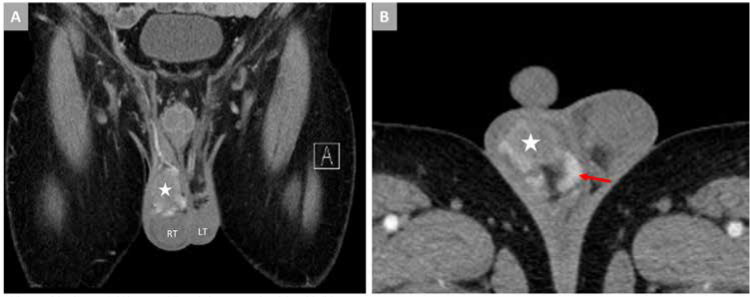

Sjögren's Syndrome Masquerading as Testicular Vasculitis.

伪装成睾丸血管炎的斯约格伦综合征